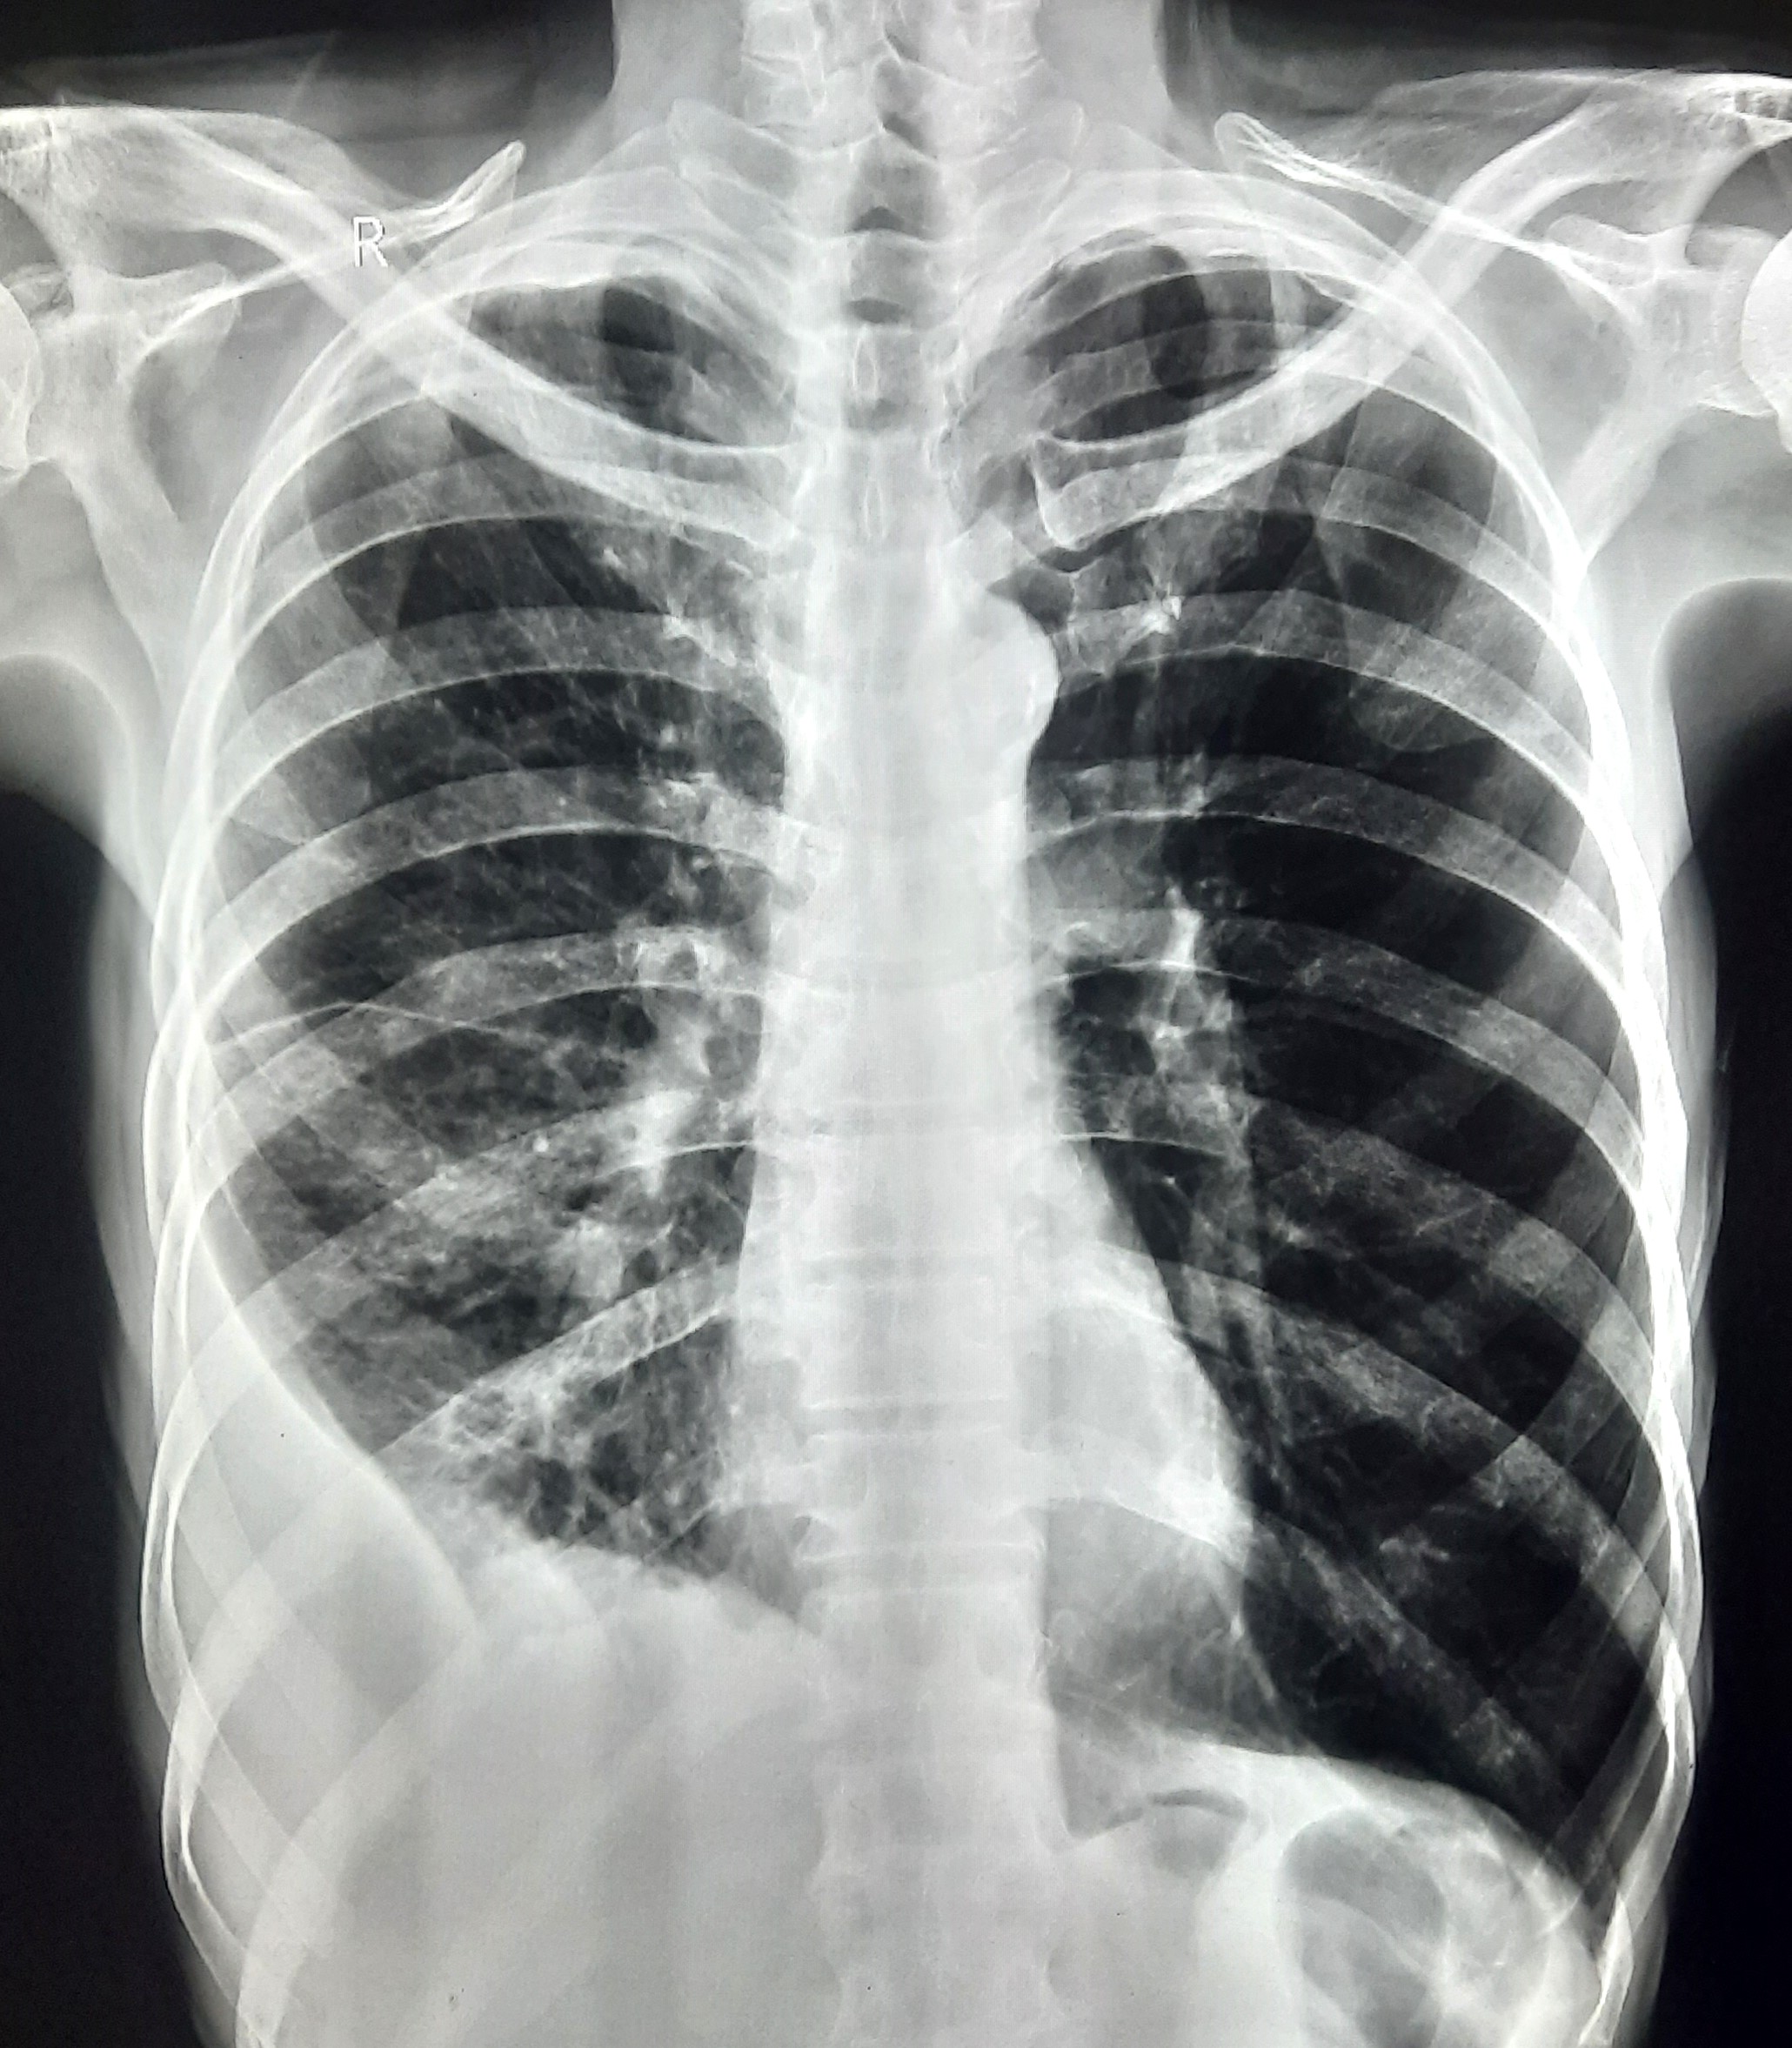

| 102 | IGGMC, Nagpur, Nagpur | P2 | 29-4370 | Prachi Bawane | Consent taken on Paper | 17 Yrs. |

Provisional Diag : PTB?

Final Diag : Active Pulmonary Tuberculosis With Tuberculi? Right Sided Pleural Effusion |

TB Case (Confirmed) | Bilateral ill Defined, No Homogenous Reticulonodular opacities, Right CP Angle Blunting | Abnormality visible on x-ray |